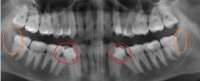

image.png 542Кб, 1538x626

Был у ортодонта-челюстного-ортопеда. Сказала что каппу без передних зубов опасно дольше 2 недель носить и зубы передние начнут вылезать вниз и прикус испортится ещё больше. Сказала нужно удалить нижние два зуба мудрости т.к. в них она увидела белые пятна рядом - признак воспаления...А вдруг это ваще всё с самого начала из-за них? Хотя боли чаще именно в верхней части челюсти, а нижня никада не болит...И почему другие врачи на это воспаление не указали?...Ну и рентген старый, ему год уже..

Аноним 20/08/24 Втр 16:07:52 1563535 35

Черные пятна* фикс